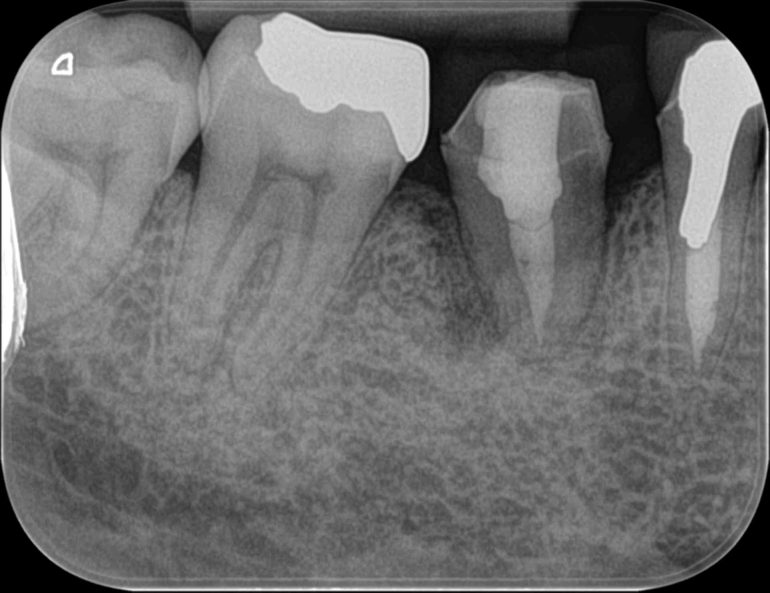

移植後2ヶ月。歯の周囲に骨の模様が見えてきています。ここまでくると歯の動揺はわずかになっています。

移植後4ヶ月で最終補綴装置(被せ物)を装着したところです。きれいに骨ができているのがわかります。